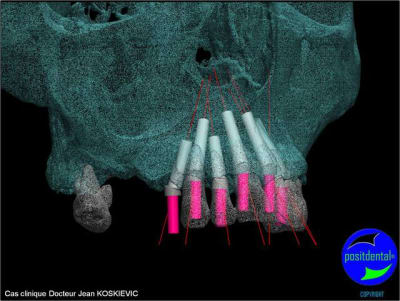

chirurgie à venir

> chirurgie à venir

Béotien, le guide chirurgical est dispositif médical sur mesure, c’est la raison pour la quelle j’ai choisi de le concevoir et réalisé en acier chirurgical, il peut ainsi être stérilisé pour correspondre aux recommandations de la HAS (haute autorité de santé), son design et étudié pour facilité l’irrigation externe, les outils connexe soit standard soit développés spécifiquement par Positdental ont le marquage CE et ma qualité de prothésiste dentaire m’autorise à remplir le certificat de conformité répondant aux exigences relative à directive européenne n° 93/42 CEE. Pour la deuxième question une formation clinique et théorique par des praticiens sous l’égide du Docteur Jean KOSKIEVIC et technique ainsi que des cas cliniques accompagnés se met en place. En effet l’implantation bi maxillaire est complexe et demande beaucoup d’attention.

et la projet 10 implants maxillaire sup